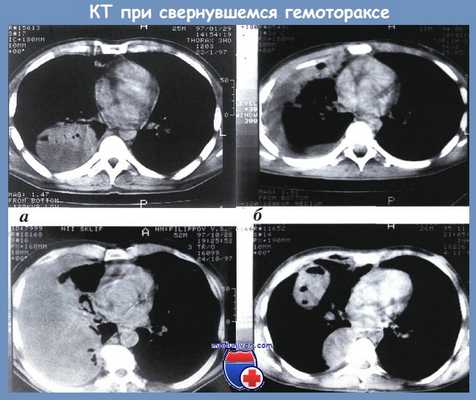

КТ органов грудной клетки. Геморрагическое содержимое в грудной полости слева, воздух в грудной полости слева, поджатое левое легкое